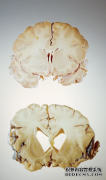

在人类形式的疯牛病中,称为克雅氏病,一个人的大脑会恶化确切地说,大脑会出现空洞,导致痴呆症迅速发展。90%的病例在一年内死亡。...

神经科学研究中最有趣的新领域之一是发现与阿尔茨海默病、帕金森病和其他神经退行性疾病有关的蛋白质可以扭曲成错误的形状。这种畸...